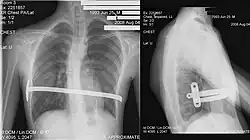

Metoda Nussa

Polega na wprowadzeniu pod mostek jednej do trzech chromowo- niklowych płyt, po obróceniu których wypycha się zapadnięty mostek (do poziomu wystających żeber) redukując deformację. Cięcia robi się w linii pachowej długości ok. 2 cm, płytki wyjmuje się po ok. dwóch latach od ich założenia. W przypadku alergii na nikiel istnieje możliwość użycia płyt tytanowych. Metoda ta u dorastających pacjentów prowadzi do dobrego efektu kosmetycznego. Ryzyko nawrotu wady jest znikome. [9][10]